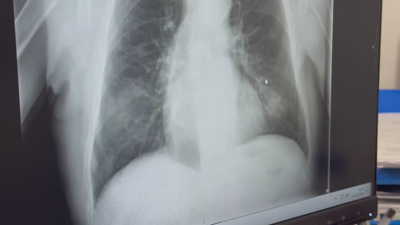

No #DiaMundialContraoCancro, en Zona mixta contaron coa testemuña de Juan Caneda, que sufriu un cancro que lle fixo ser transplantado de medula. Iso non lle impediu volver ao fútbol.

Cando lle din que ten leucemia linfoblástica aguda, Juan sofre un shock: "Claro que tes medo a morrer", pero afortunadamente un dos seus irmáns era compatible para doarlle a medula e finalmente se atopa moito mellor